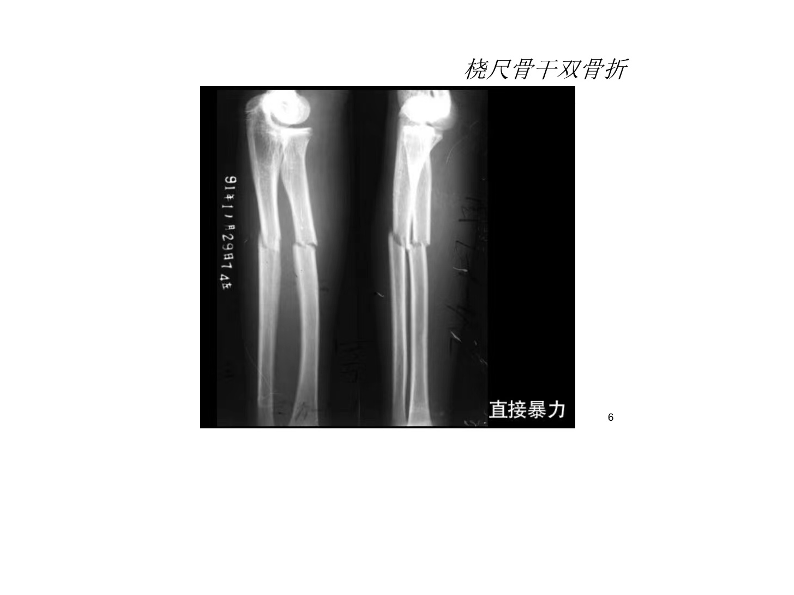

桡尺骨骨折